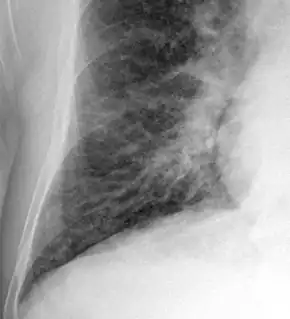

Ultrasound of the lungs showing edema due to severe systolic heart failure[38]

Chest X-ray

Chest X-rays are frequently used to aid in the diagnosis of CHF. In a person who is compensated, this may show cardiomegaly (visible enlargement of the heart), quantified as the cardiothoracic ratio (proportion of the heart size to the chest). In left ventricular failure, there may be evidence of vascular redistribution ("upper lobe blood diversion" or "cephalization"), Kerley lines, cuffing of the areas around the bronchi, and interstitial edema. Ultrasound of the lung may also be able to detect Kerley lines.[39]

Kerley b lines.